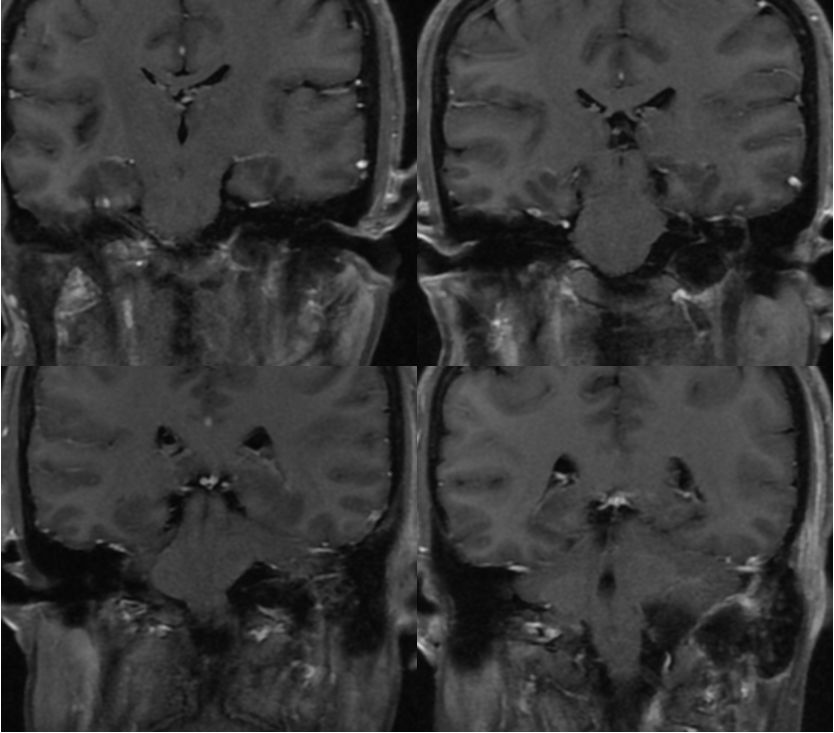

术中过程

![]()

切口体位